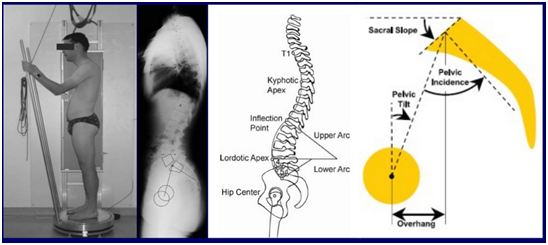

- Psychological assessment of elderly is very valuable before major surgery (Figure 5,6).

Figure 5 Whole spine x ray films in coronal and sagittal planes.

Figure 6 Spino-Pelvic alignment.

PI = PT + SS

Pelvic incidence fixed anatomical value no matter what the position of the pelvis is

Angle between a line joining the center of the upper endplate of s1 to the axis of the femoral heads and a line perpendicular to the upper end plate of s1.2 (Figure 7).

Sacral slope

Angle between the endplate of s1 and a horizontal line.

Pelvic tilt

Angle between a vertical line and the line joining the middle of the sacral plate and the axis of the femoral heads.